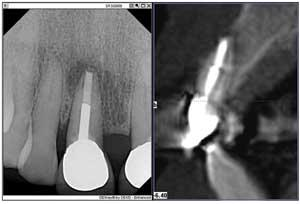

Here's where the second part of the duo, my CBCT system, came to my rescue. The 3-D image provided the further evidence of a horizontal root fracture.

Furthermore, the radiolucency extended both mesially and distally, and the lesion had invaded the facial plate, necessitating a more extensive surgery — good to know before making the incision. The 3-D scan presented me with a clear image of the extent of the bone destruction, the need for a bone graft, and the possible additional need for a membrane.

Before seeing all the facts, the patient was apprehensive; after all, it was her front tooth. The digital PA X-ray supported the need for the scan, and the scan verified the situation to the patient in detailed 3-D imagery. Before this technology was available, I didn't know what I would find after the incision, and the patient could feel that uncertainty. Without this additional information, my conversation included a lot of “we might have to do this,” or “we might have to do that.”

When I showed the patient the 3-D image, while zooming in or rotating the tooth 360 degrees, she could see the bone, the damage, and the size of the space, relieving her fear of the unknown and freeing her mind so she could participate in her treatment planning. We were both relieved to know the extent of the surgery before starting the procedure. Knowing the full extent of the damage beforehand is like seeing the future through a crystal ball.